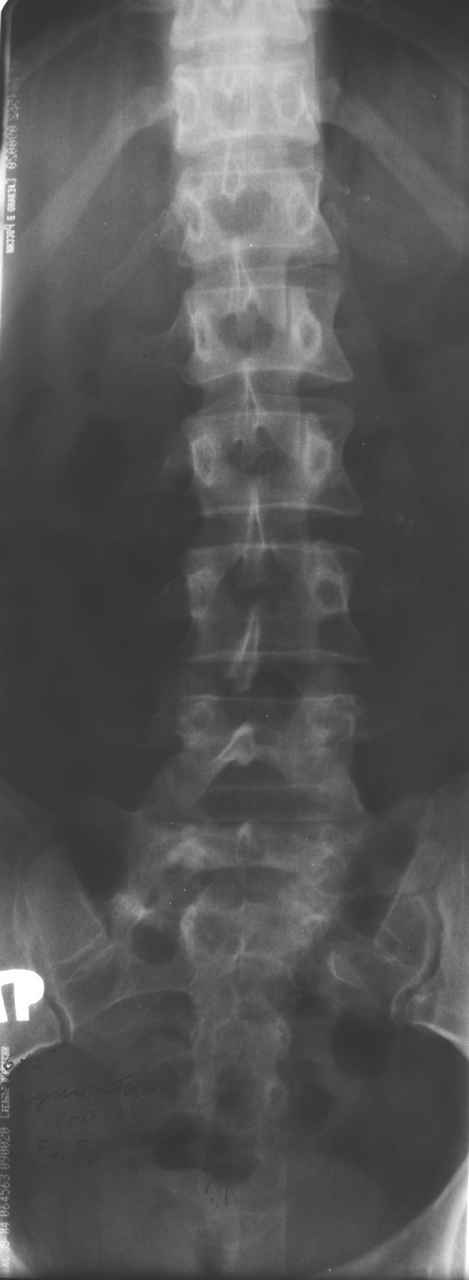

13/03/03 |  13/03/03 |  13/03/03 |  15/09/06 |  15/09/06 |  07/03/07 |  07/03/07 |  19/12/06 | К нам в клинику поступила пациентка 30 лет с диагнозом: Постравматическая ротационная стабильная деформация тазового кольца. Относительное укорочение левой н\конечности на 1 см. Левосторонний компенсаторный сколиоз 2 ст. Болевой синдром. травма автодорожная в январе 2003г. Пассажирка переднего сидения ваз 2109. лечились положением по Волковичу. С марта 2003 года жалуется на боли в тазу, ппояснице усиливающиеся при движении.В настоящее время жалобы на боли в области крестца, КПС больше слева, в пояснично-крестцовом отделе позвоночника. неприятные ощущения, щелчок при выпрямлении правого тазобедренного сустава из положения полного сгибания. боли в тазу появляются при ходьбе ч\з 100 м, так же при вставании из положения сидя, после сидения в течении 2-3 часов. при ходьбе более 100 м появпяется зябкость стоп больше справа. ходит при помощи трости в правой или в левой руке. без трости боли появляются сразу после начала ходьбы. пальпация болезненна в паравертебральных точках средне-грудного и пояснично-крестцового отделов позвоночника, КПС с обеих сторон. Объем движений в тазобедренных суставах полный.правый КПС заблокирован. симптомы натяжения с обеих сторон отрицательны.С 2003г. лечится консервативно, получала ЛФК, массаж, физиолечение - без эффекта. в 2005г. лечилась в санатории с ортопедическим уклоном, получала плавание в минеральной воде, магнитотерапия, массаж, ЛФК. отмечала умеренное улучшение в течении 2 недель.Вопросы:надо ли оперировать, т.е. устранять относительное укорочение левой н\конечности и как?Если не оперировать, то как лечить консервативно?Р-граммы, КТ прилогаются.

Проблема Вашей пациентки находится на границе интересов специальностей ортопедия (вертебралогия) и неврология (нейрохирургия), вероятно, поэтому так мало откликов на ваше обращение. Представленные рентгенограммы не все информативны (особенно спондилограммы от сентября 2006 года). Вероятно, необходимы дополнительные методы исследования к.т. МТГ, ЯМРТ, миелография.

просьбе. досылаю КТ, фуккциональные Р-граммы пояснично-крестцового отдела позвоночника, фото пациентки.

Здравствуйте уважаемые коллеги. Высылаю обещаннное ЯМРТ. Никаких нарушений м\позвонковых дисков, мяггкотканных образований на уровне Th12-S3 не обнаружено.